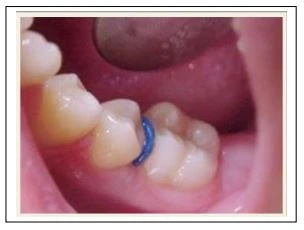

1.1. Chun tách khe:

Rẻ và rất dễ sử dụng ở trẻ em và thanh niên. Ở những điểm tiếp xúc chật, có chứa miếng trám bạc amalgam, thì chun tách khe dễ bị đứt lúc đưa quá điểm tiếp xúc. Có vẻ như chúng cản trở khớp cắn, không cho phép bệnh nhân cắn chặt hai hàm lại với nhau. Do cản trở khớp cắn như vậy cộng với lực mạnh từ vật liệu Polyurethane đặt vào răng gây ra những cảm nhận đầu tiên về lực, rất nhiều bệnh nhân sẽ than phiền vì đau. Vì lý do này chúng ta thường không sử dụng chun tách khe ở người lớn, những đối tượng nhậy cảm với đau cản trở khớp cắn hơn.

Chúng tôi khuyên bạn dùng là loại chun tách khe cản quang, có thể dùng được khi chụp phim x-quang.

Cách đặt chun tách khe:

a. Bằng kìm đặt chun: Nhẹ nhàng, nhanh, ít gây khó chịu cho bệnh nhân nhất.

b. Dùng chỉ tơ:

c. Dùng kẹp Mosquito